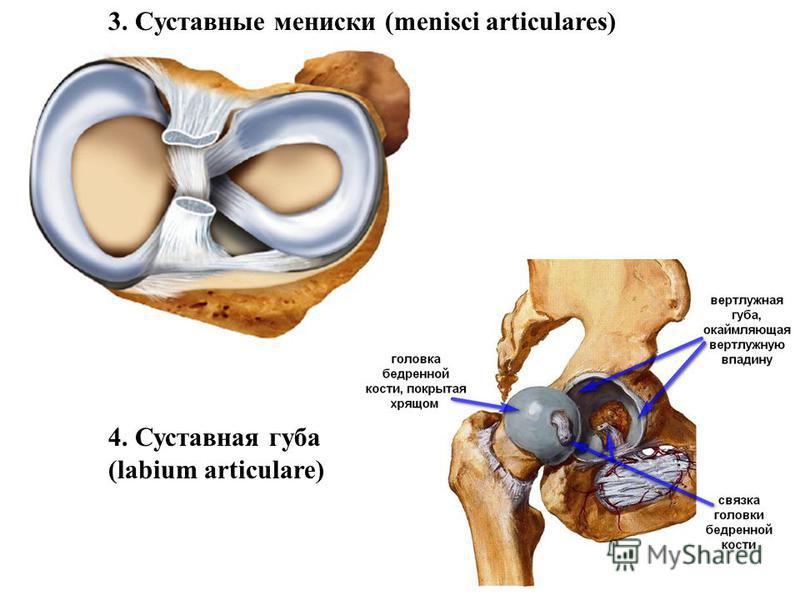

Анатомические изображения менисков и коленного сустава